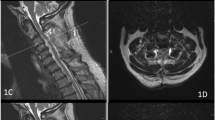

Objective: Aggressive anterior debridement and fusion has been advocated for the treatment of cervical osteomyelitis/epidural abscess (COEA) for many years. In this study we review our experiences with severely neurologically impaired (tetraplegic) patients with COEA.

Methods: From 1989–1999 we identified 20 cases of COEA treated with anterior debridement and fusion. Patients were identified from a prospectively maintained database. All inpatient and outpatient records were reviewed. Six patients were identified as being tetraplegic prior to surgery. Tetraplegia was defined as complete absence or only flicker movement of the extremities.

Results: The age range was 41 to 74. There were five men and one woman. Anterior corpectomy and fusion with either iliac crest auto- or allograft was performed in all patients. In four of six patients an anterior cervical plate was utilized for internal fixation. Four of six patients were ambulatory at last follow-up.

Conclusion: Aggressive debridement and fusion in patients with COEA can result in successful outcomes even in patients who are tetraplegic prior to surgery.